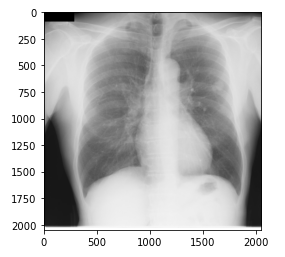

画像ファイルは、前にダウンロードした練習用データセットを展開すると、「PNG」形式のフォルダがでてくる。今回は、このPNGファイルで読み込みと表示を行う。

img01=cv2.imread("./chestimage_PNG/JPCLN001.png")

plt.imshow(img01)

plt.show()

OpenCVのimredメソッドを使って、フォルダ内の画像を指定し表示させる。

表示画像は、サンプルの1つをピックアップしている。

表示結果としては、次のようになる。